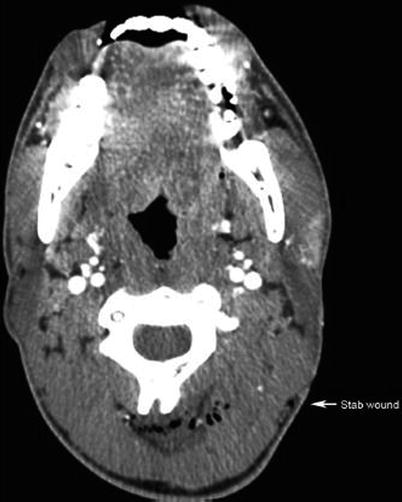

Fig. 16.6

Stab wound to the left posterior neck clearly showing wound tract without evidence of proximity to vascular structures